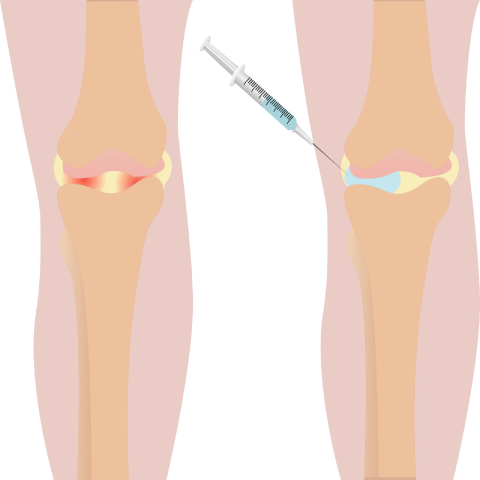

연골주사 (히알루론산)

우리 몸의 윤활액과 비슷한 성분으로 합성한 약물을 관절강 내 직접 주입해 윤활작용을 촉진하는 치료입니다. 히알루론산 성분은 관절 간의 마찰을 줄여줘 손상된 연골을 보호하고 마모를 늦춰 퇴행성 무릎 관절염 증상을 완화시켜줍니다.

연골주사 적응증

□ 무릎, 어깨 관절의 초기 관절염

□ 무릎, 어깨 관절염